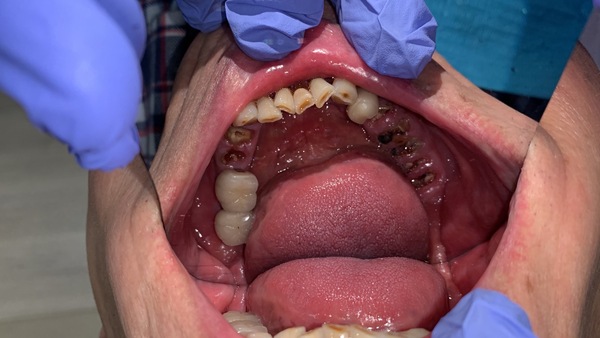

因距此位患者前一次修復牙齒已十幾年了,患者十幾年來放任牙齒不管,斷了就放著不理,或者拔牙後就不修復。

所以牙齒多處局部都受力過大,有斷裂風險。

以下案例為與上面相同年齡,七十初頭歲。

前兩年患者認為自己身體狀況不好,決定牙齒只要壞了,就用活動假牙就可以,不想再花時間和金錢修復牙齒,太累太辛苦了。

奈何牙齒每況愈下,抽了神經後,陸續斷牙,直到累計滿5顆,真的無法再忍耐了。

但患者嘗試過了,覺得活動假牙不好用、很麻煩,且能咀嚼食物有限,因此回頭想要知道有沒有更好的方法可以修復,但不要太長時間的方法。

所以我們常在患者約50-60歲時建議患者要好好考慮,重建牙齒的時機,以免七十歲以上面臨選擇時會左右兩難,畢竟牙齒要一直跟著我們使用到最後一刻,有沒有牙齒,真的差很多,不管是食物的攝取、發音、容貌、自信,所以聰明的患者,一定要提早規畫好自己的老年生活。